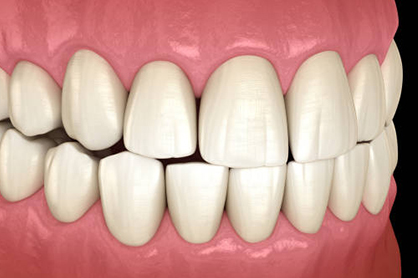

We believe in a collaborative approach when it comes to your final teeth. You, the dentist, and our lab technician will work together to create your perfect smile. Unlike other offices that use acrylic denture teeth over titanium bars, we use zirconia for superior appearance, durability, and resistance to staining. While other offices may charge extra for these materials, at Cedar Grove Dental Group, they are standard.

Custom-Made

- We custom made all the teeth for each Patient.

- No RETRO-FITTING is needed.

Custom-Made (OUR)

- Match to Existing Natural Gum Tissue